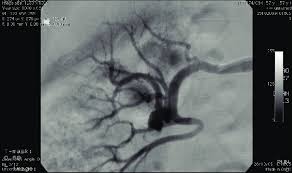

Aneurisma - File Aneurisma Micotico De La Arteria Iliaca Izquierda Jpg Wikimedia Commons

Aneurisma - File Aneurisma Micotico De La Arteria Iliaca Izquierda Jpg Wikimedia Commons. Un aneurisma cerebral no suele cursar con síntomas, pero es vital conocer toda la información para estar prevenidos y saber cómo actuar. Learn about detection, diagnosis, treatment options and advances for brain aneurysm, including surgical clipping, endovascular coiling and flow diverters. Los aneurismas pueden ser hereditarios o causados por enfermedades que debilitan las paredes de los vasos sanguíneos. Aneurysms may be a result of a hereditary condition or an acquired. Because of the constant pressure of the circulating blood within the artery, the.